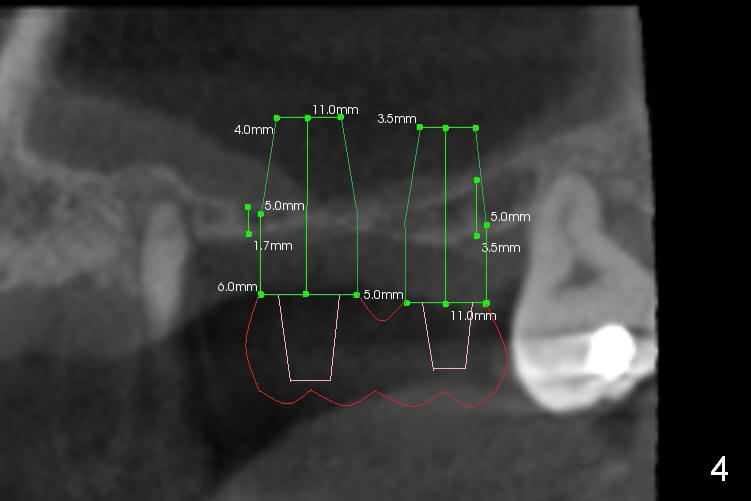

A 45-year-old man has lost #14 and 15 for a while. The sinus floor is 2-3 mm (Fig.1 (CBCT sagittal section), 2,3 (coronal sections)). The sinus membrane will be lifted by lateral window approach (Fig.2,3). With Metronidazole (prevent postop sinus infection) and 2% Xylocaine 1:50,000 gauze inserted underneath the sinus floor, osteotomy is initiated from the crest using UF cassette drills. Two of 5-6.5x8 mm implants will be placed, followed by immediate cemented abutments. Pack bone graft before and after implantation. Prepare both a syringe of Osteogen and allograft. The splinted immediate provisional will strengthen primary stability of the implants (Fig.4). The distal root caries of #13 (Fig.1 *) has been fixed as well as root canal therapy (Fig.5).